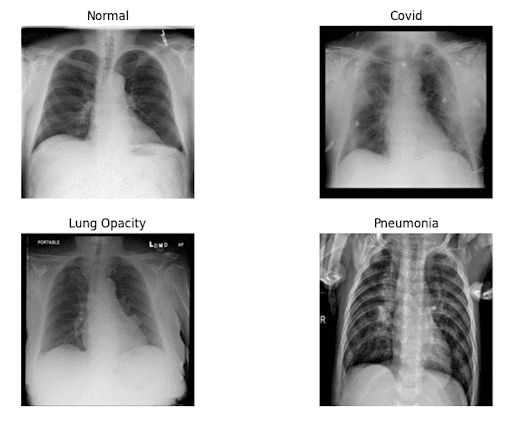

Ground Truth CT Scans